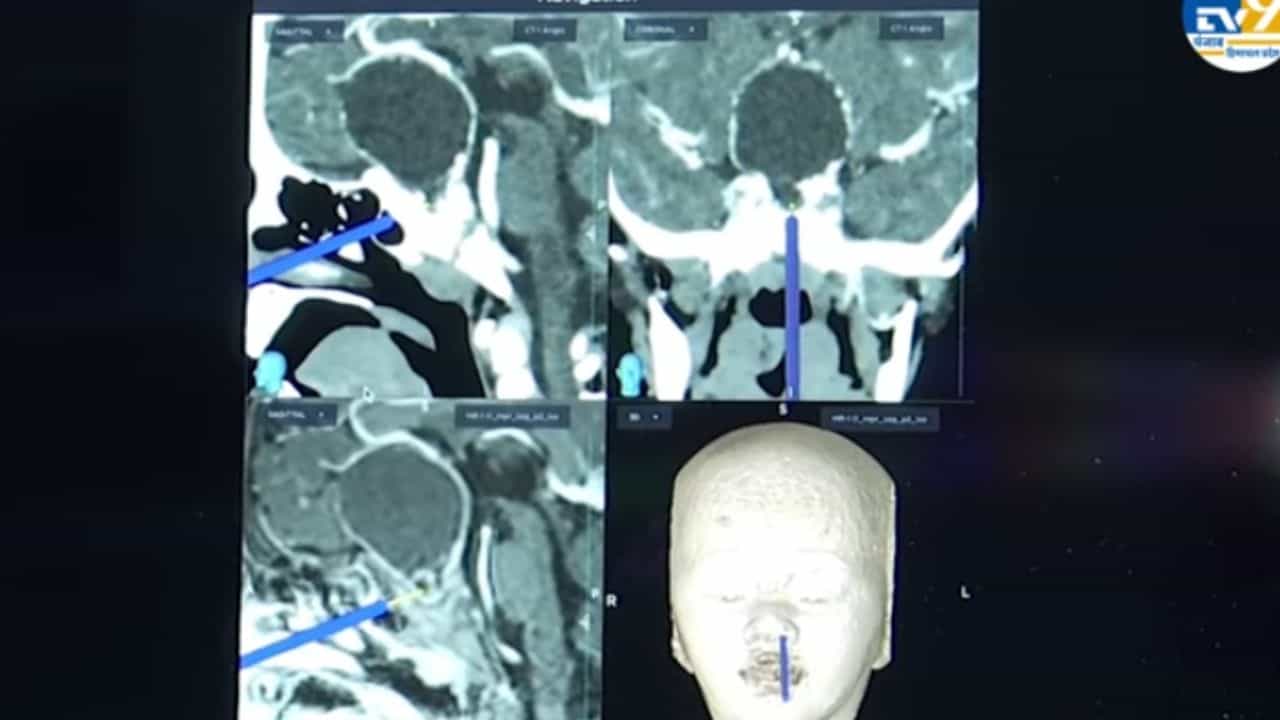

Chandigarh PGI: ਚੰਡੀਗੜ੍ਹ ਪੀਜੀਆਈ ਦੇ ਡਾਕਟਰਾਂ ਨੇ ਨੱਕ ਰਾਹੀਂ 2 ਸਾਲ ਦੀ ਬੱਚੀ ਦੇ ਦਿਮਾਗ ਵਿੱਚੋਂ 4.5 ਸੈਂਟੀਮੀਟਰ ਦਾ ਟਿਊਮਰ (ਕ੍ਰੈਨੀਓਫੈਰਿੰਗੀਓਮਾ) ਸਫਲਤਾਪੂਰਵਕ ਕੱਢਿਆ ਹੈ। ਇਹ ਦੁਨੀਆ ਦਾ ਦੂਜਾ ਮਾਮਲਾ ਹੈ ਜਦੋਂ ਇੰਨੀ ਛੋਟੀ ਬੱਚੀ ਦੇ ਸਿਰ ਨੂੰ ਖੋਲ੍ਹੇ ਬਿਨਾਂ ਨੱਕ ਰਾਹੀਂ ਇੰਨੇ ਵੱਡੇ ਬ੍ਰੇਨ ਟਿਊਮਰ ਨੂੰ ਕੱਢਿਆ ਗਿਆ ਹੈ। ਦਰਅਸਲ ਡਾਕਟਰਾਂ ਨੇ ਇਸ ਆਪਰੇਸ਼ਨ ਲਈ ਐਂਡੋਸਕੋਪਿਕ ਤਕਨੀਕ ਦੀ ਮਦਦ ਲਈ ਹੈ। ਕੀ ਹੈ ਇਹ ਤਕਨੀਕ ਅਤੇ ਕਿਵੇਂ ਕੰਮ ਕਰਦੀ ਹੈ। ਜਾਣਨ ਲਈ ਵੇਖੋ ਇਹ ਖਾਸ ਵੀਡੀਓ…